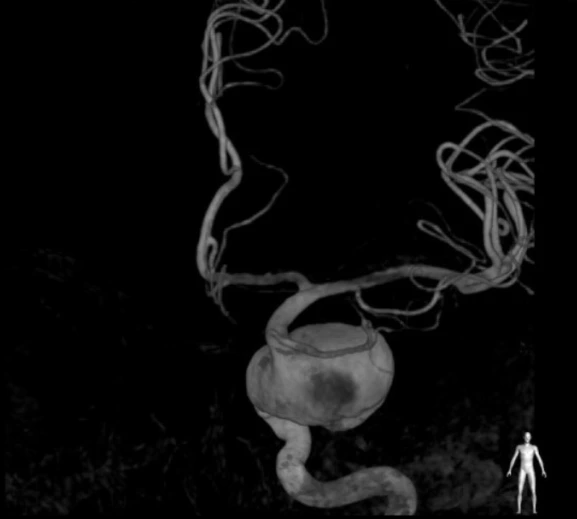

이후 혈관조영술이라는 더 내혈관을 자세히 볼수 있는 시술을 마친후에 내 머릿속에 "거대 뇌동맥류" 라는것이 있는걸 확인할수 있었다.

"저렇게 되기전에 혈관이 터져서 뇌출혈이 오고는 하는데 , 정말 운이 좋았다고 밖에요.. 혈전(선지같은거)이 점점 늘어나면서 터지지않고 부풀기만 했었습니다."